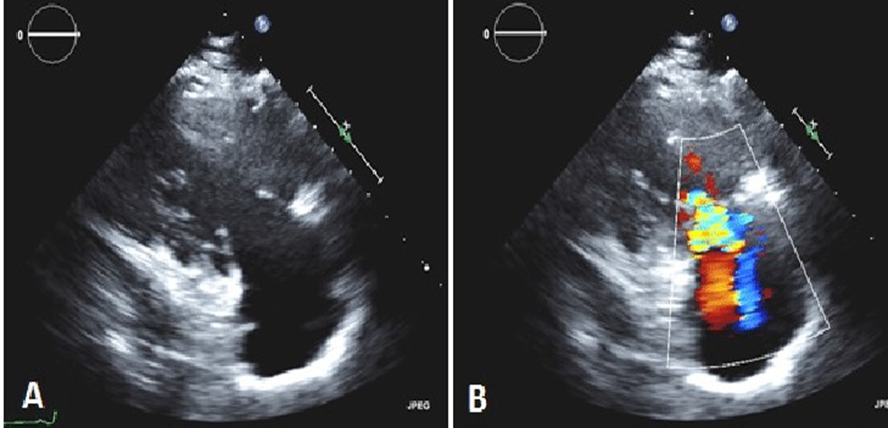

Where is the tricuspid valve located in this image?

On an echocardiogram this presents a thickening and retraction of the tricuspid valve leaflets during systole. The right-sided image demonstrated severe tricuspid valve regurgitation.

Tricuspid Regurgitation Color Jet

Assess TR jet width and length in all views. Adjust color gain, scale, and color box

Views in RVIT, SAX AO, A4C